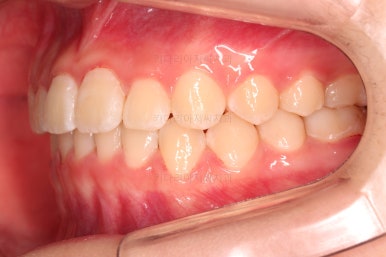

1. 초진

초진 시 입안의 모습입니다.

눈에 띄는 부분은 당연히 앞니가 삐뚤고, 앞니 하나가 앞으로 튀어나온 모습인데요.

자세히 관찰해 보면 다른 문제점들이 보입니다.

우선 위아래 앞니가 깊숙히 맞물려 있는 과개교합 양상인데요.

✅ 앵글씨 2급 부정교합

이번 환자분은 앵글씨 2급 부정교합이었는데요.

정상교합에 비해서 윗니가 상대적으로 앞에 아랫니가 상대적으로 뒤에 위치한 부정교합이 앵글씨 2급 부정교합입니다.

이번 환자분은 어금니가 위아래가 지그재그 서로 엇갈려 꽉 끼이는 교합이 아니라 1대1로 치아가 부딪혀 있는 상태였습니다.